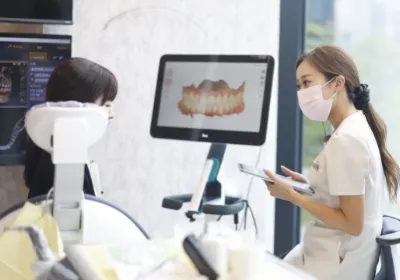

当院では、歯の専門家達が

不安を徹底的に取り除きます

歯磨きで出血することがある、なんだか食べ物が詰まりやすくなった気がするなど、普段の生活の中で気になった些細な違和感が歯周病の初期症状である可能性もあります。

当院では、経験豊富な歯科医師や歯科衛生士、歯の専門家達が、そういった小さな不安のご相談も親身にお伺いし、丁寧な説明をさせて頂きながら、早期の検査やケアで歯周病になりにくい口内環境を作っていきます。

専用のカウンセリングルームも完備

どんな些細な違和感やご不安でも

まずはお気軽にご相談下さい。

初期症状になかなか気づきにくい歯周病ですが、

患者様がいつでも気軽にご相談や検査にお越し頂ける環境を作り、

早期発見・予防をしていただけるよう心がけております。

患者様の大切な歯がいつまでも健康なままでいられるように、

一人一人と深く向き合いながら

一緒に歩いてゆくようなお手伝いをさせて頂いております。